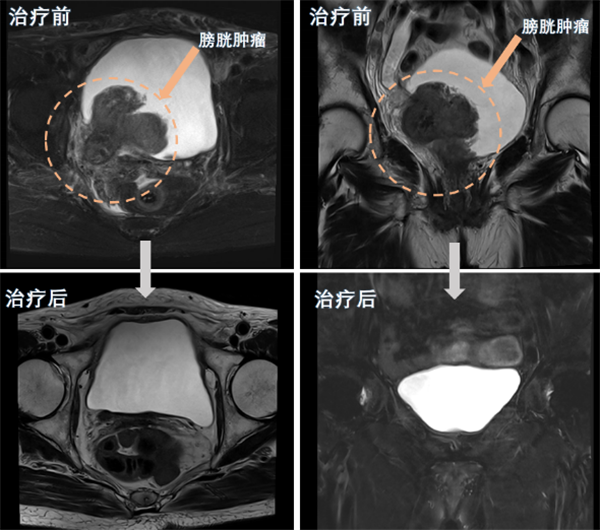

近日,老虎机app (简称老虎机app )泌尿外科团队为一名80岁高龄的巨大膀胱肿瘤患者实施了经尿道膀胱肿瘤剜除术及术后精准综合治疗,成功保住了该患者的膀胱。经过四个周期的综合治疗后,患者膀胱恢复完好,未见肿瘤复发。该手术的成功,标志着我院泌尿外科在膀胱癌诊治和保膀胱治疗技术方面取得了新突破。半年前,80岁的苏奶奶(化名)因反复无痛性肉眼血尿在当地医院就诊,经...